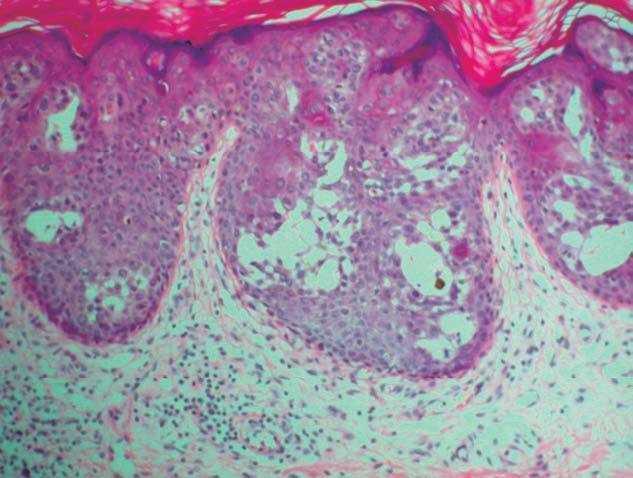

Presentamos el caso de una mujer de 88 años con varias lesiones en la región submamaria derecha, que habían permanecido estables durante más de 40 años, que refiere un rápido crecimiento y ulceración de una de ellas en el último año. En la exploración mostraba, bajo la mama derecha, una lesión tumoral de 7 cm de diámetro, de consistencia firme, superficie queratósica en periferia y ulcerada en el centro y exudación serosa maloliente. Adyacentes a ella se observaban varias lesiones tumorales de menor tamaño, con una superficie aterciopelada, de coloración eritemato-pardusca, y con una distribución lineal (fig. 1). No se palparon adenopatías loco-regionales. El estudio analítico completo, así como las radiografías de tórax, electrocardiograma, mamografía bilateral y ecografía axilar derecha, fueron rigurosamente normales. Se realizó una biopsia incisional de la lesión tumoral de mayor tamaño y otra biopsia de una de las lesiones adyacentes. En el primer caso, la tinción de hematoxilina-eosina mostró islotes irregulares anastomosados compuestos por células tumorales intraepidérmicas, algunas de ellas pigmentadas, con un citoplasma más claro que los queratinocitos circundantes. Se observaron abundantes células atípicas con núcleos grandes, irregulares e hipercromáticos dentro de las masas tumorales. En algunas secciones se podían ver espacios quísticos dentro de estos nidos de células basaloides. La epidermis presentaba hiperqueratosis, focos de paraqueratosis y acantosis irregular (fig. 2 A y B). La biopsia de la lesión de menor tamaño mostró nidos bien definidos de células cuboidales uniformes que poseían núcleos basofílicos, redondeados y no atípicos, con presencia de estructuras quísticas en su seno (fig. 3). El citoplasma de las células tumorales contenía gránulos PAS positivos en ambos casos. Las tinciones inmunohistoquímicas demostraron que los islotes tumorales se teñían con anticuerpos monoclonales frente a las citoqueratinas AE1/AE3, 34betaE12 y EMA, y no presentaron reactividad para las citoqueratinas 7, 20, CAM5.2, CEA y GCDFP15. Se realizó el diagnóstico de hidroacantoma simple maligno (HSM) sobre un hidroacantoma simple (HS) de distribución lineal; el tumor maligno ulcerado fue extirpado quirúrgicamente. Un año y medio después del diagnóstico, la paciente permanece asintomática y sin evidencia de metástasis a distancia en los seguimientos realizados, que incluyeron una exploración física trimestral y una analítica de sangre, una radiografía de tórax y una ecografía abdominal semestrales.

Figura 2 (A y B). Nidos de células tumorales localizadas en el seno de una epidermis acantósica que muestran atipia y mitosis (hematoxilina-eosina, x20, y hematoxilina-eosina, x100, respectivamente).